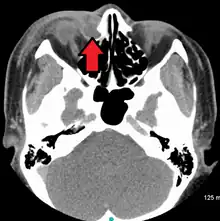

| A case of dacryocystitis as seen on CT scan | |

Dacryocystitis is an infection of the lacrimal sac, secondary to obstruction of the nasolacrimal duct at the junction of lacrimal sac.[1] The term derives from the Greek dákryon (tear),[2] cysta (sac), and -itis (inflammation). It causes pain, redness, and swelling over the inner aspect of the lower eyelid and epiphora. When nasolacrimal duct obstruction is secondary to a congenital barrier it is referred to as dacryocystocele. It is most commonly caused by Staphylococcus aureus and Streptococcus pneumoniae.[3] The most common complication is corneal ulceration, frequently in association with S. pneumoniae.[3] The mainstays of treatment are oral antibiotics, warm compresses, and relief of nasolacrimal duct obstruction by dacryocystorhinostomy.[3]